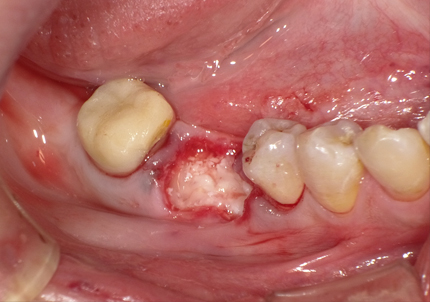

5.インプラント埋入(2021年6月)

※ 初期固定35N/cm確認する